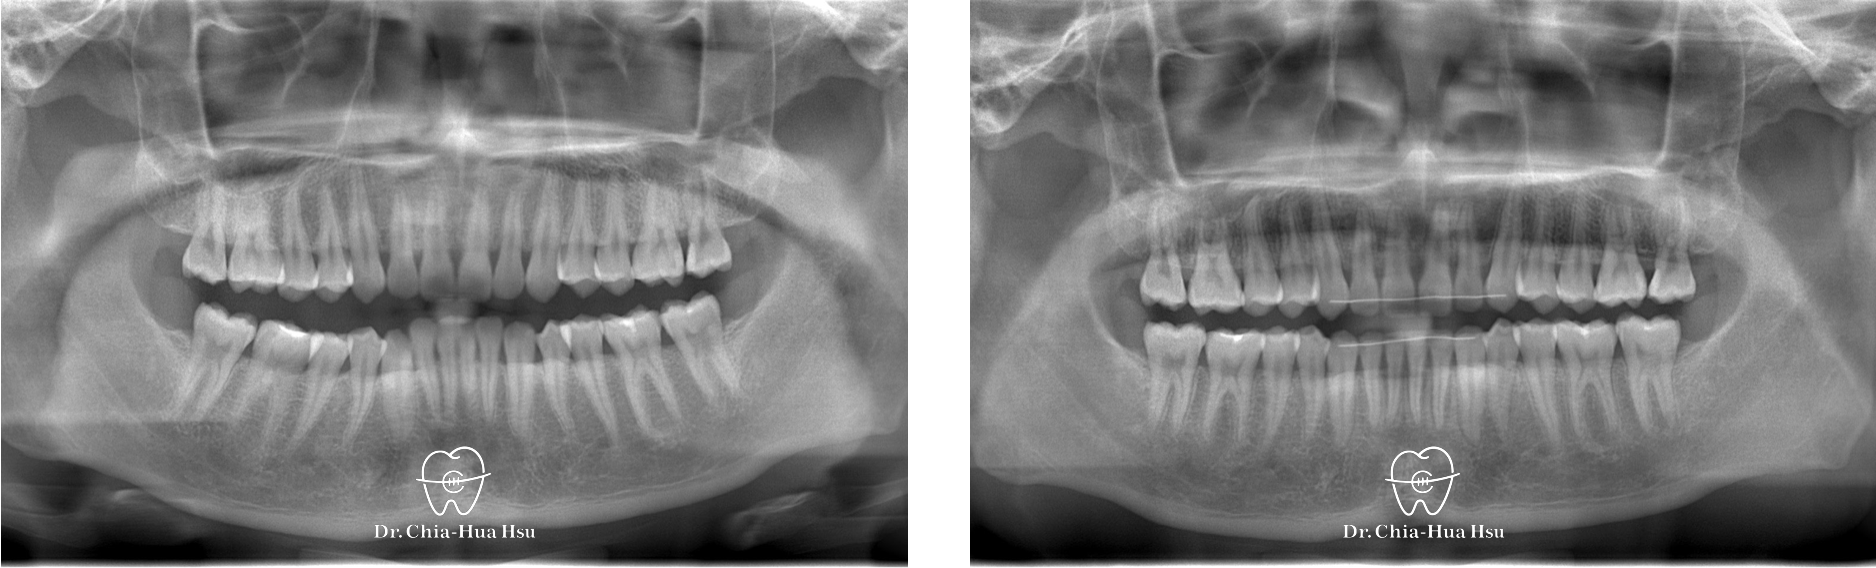

治療前

治療後

治療前

治療後